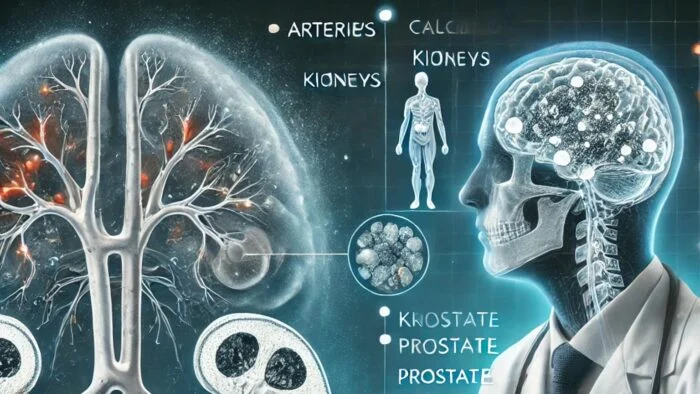

آیا کلسیفیکاسیون خطرناک است؟

آیا کلسیفیکاسیون خطرناک است؟ کلسیفیکاسیون یکی از فرایندهای طبیعی بدن است که در آن کلسیم در بافتهای نرم بدن رسوب میکند. این پدیده ممکن است در قسمتهای مختلف بدن مانند شریانها، کلیهها،…

آیا کلسیفیکاسیون خطرناک است؟

آیا کلسیفیکاسیون خطرناک است؟ کلسیفیکاسیون یکی از فرایندهای طبیعی بدن است که در آن کلسیم در بافتهای نرم بدن رسوب میکند. این پدیده ممکن است در قسمتهای مختلف بدن مانند شریانها، کلیهها، مفاصل، پروستات و مغز رخ دهد. بسیاری از افراد هنگام مشاهده…